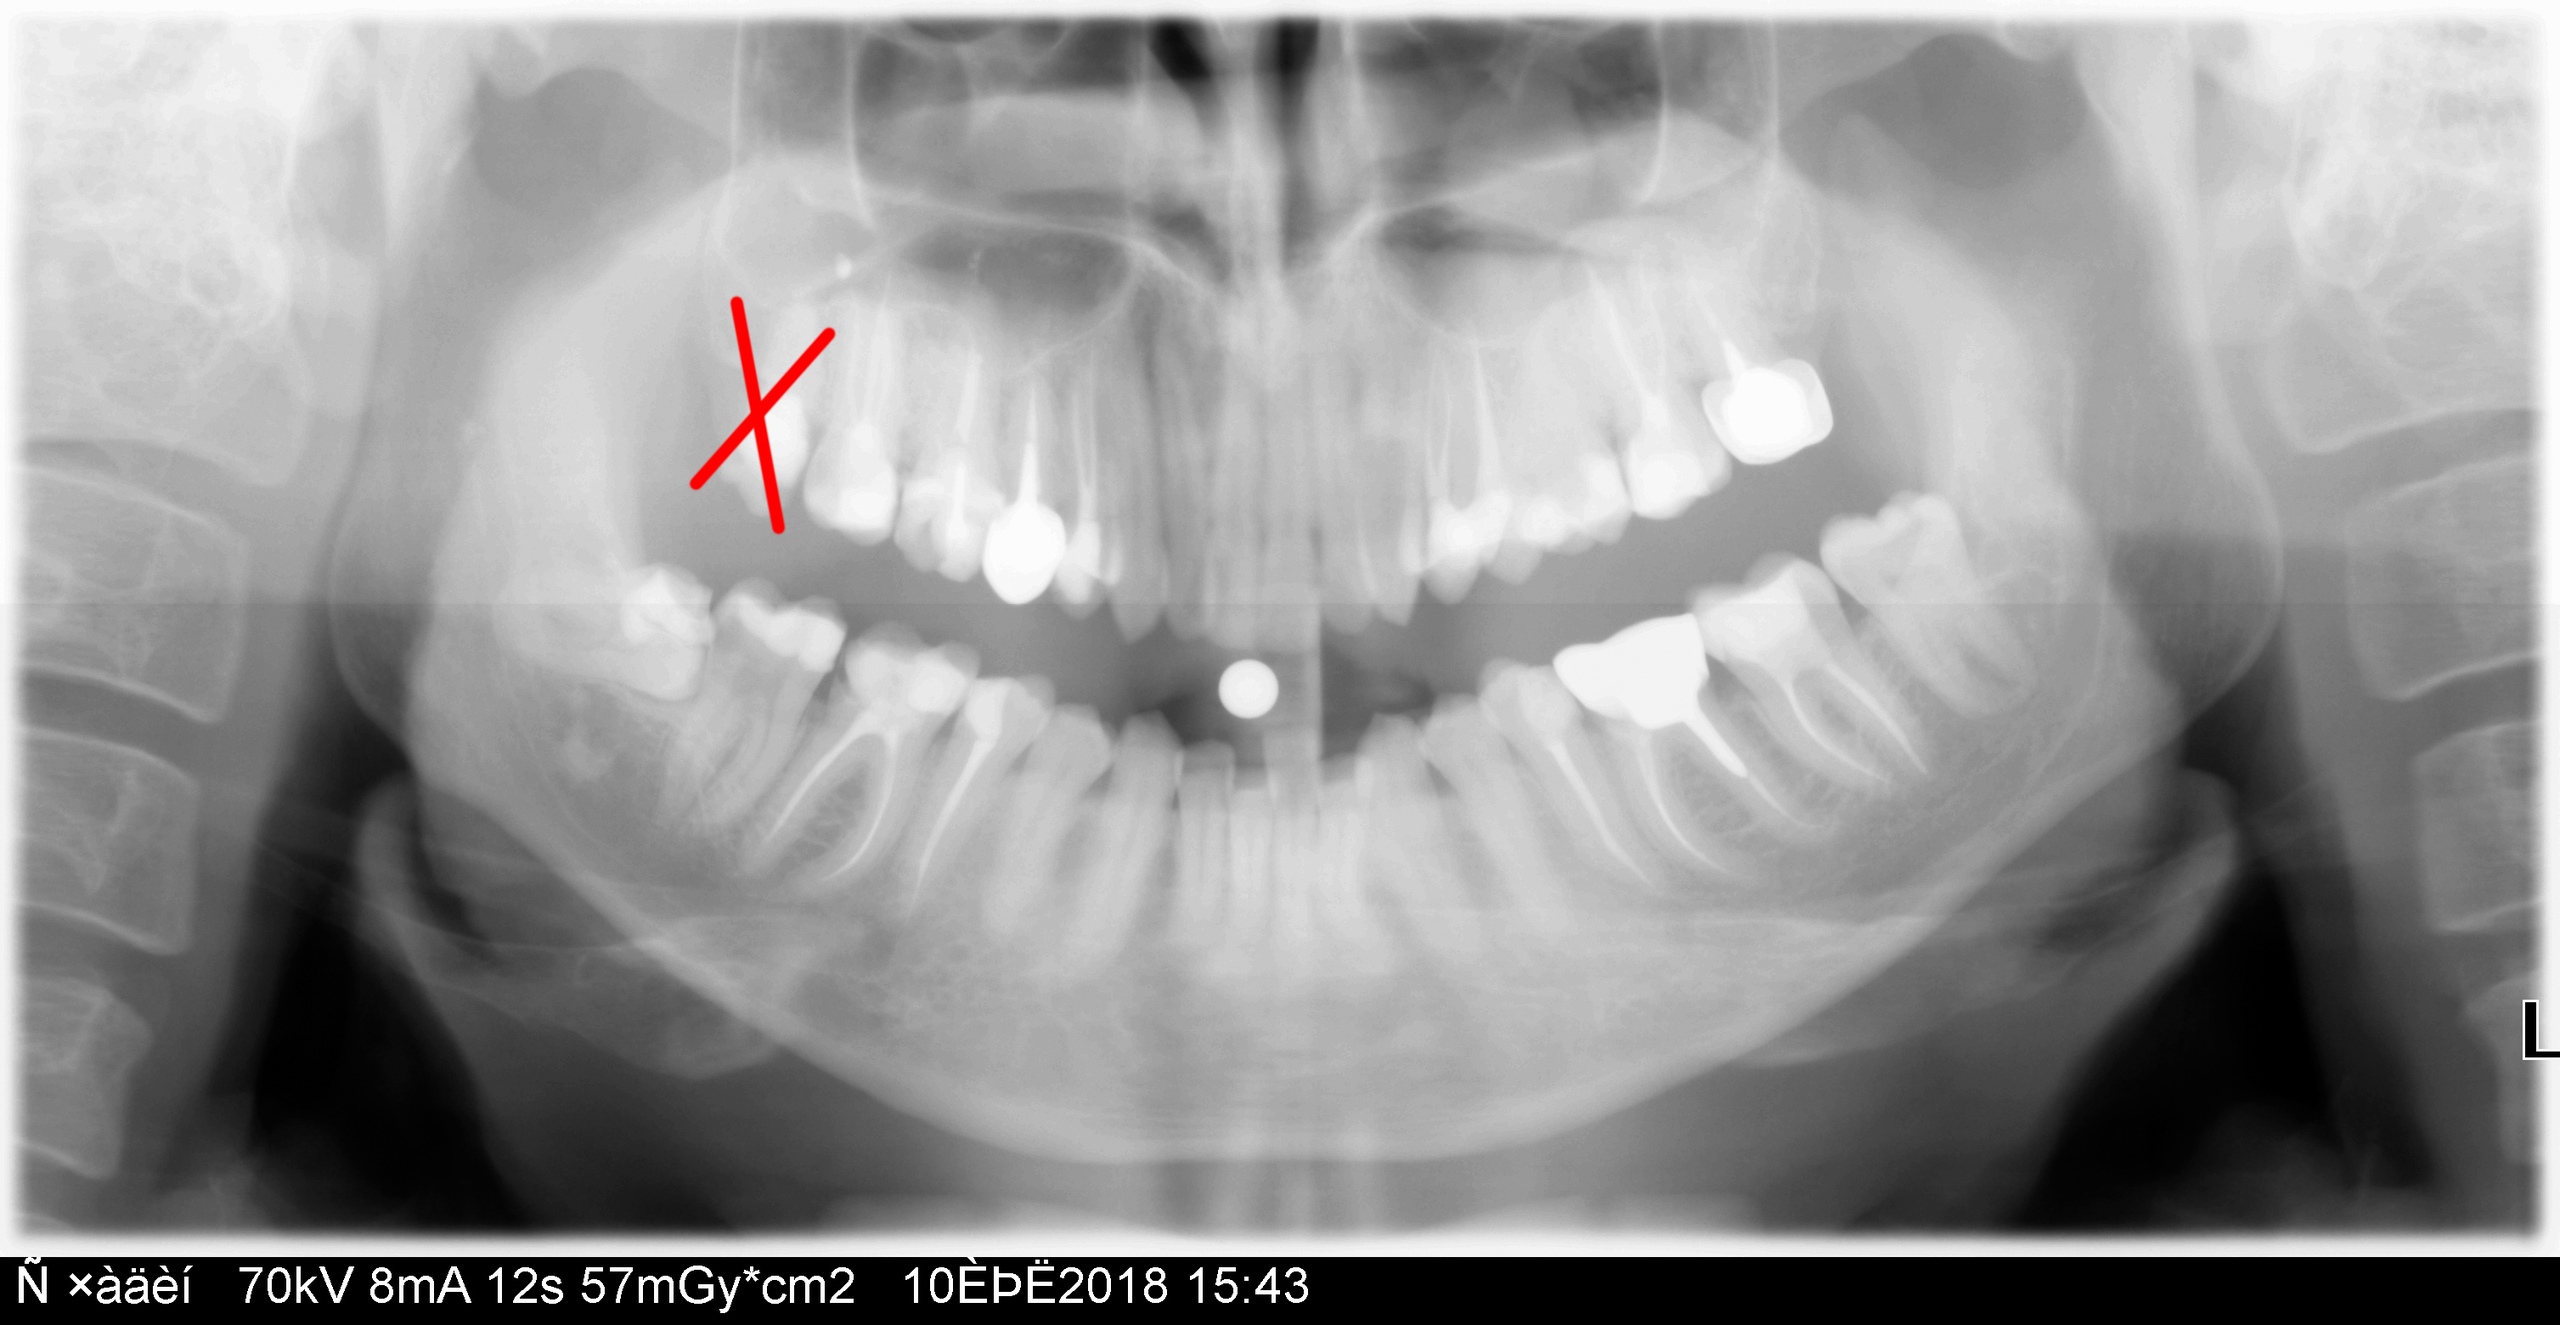

Привет. Это я. Улыбаюсь вам своими тридцатью одним зубом:

Жалко зубик :( Оказывается, рвать зубы совсем не больно и не страшно. Я почувствовал только как с карты сняли 4550 рублей, больше ничего не почувствовал. Дорого, но условия конечно чуть получше, чем на Ульяновском, где вам после стояния в 6 утра в очереди за талончиком (!!!), а потом ещё одного стояния в очереди посреди дня, хирург разворотит вам на хуй рот за 500 рублей. Посмотрю ещё как заживать будет. Какие-то конские снотворные колят, я пиздец пересрал, когда мне укололи и сразу же полезли зуб шевелить. А так норм, клиника с новыми технологиями ниибацца, сверхстерильностью, натурально операционной, блять и хирургом около 50-ти лет от роду, забитым татухами по самое не хочу. Не, можете орать на сумму, но мне там норм. |